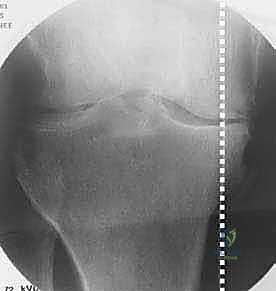

في الحالة الطبيعية الميكانيكية، يمر "محور تحمل الوزن" (Weight-bearing axis) مباشرة عبر منتصف الركبة، مما يوزع الضغط بالتساوي. ولكن، عند حدوث تقوس في الساقين (Varus Deformity)، ينزاح هذا المحور إلى الداخل، مما يضع ضغطاً هائلاً ومدمراً على الغضروف الداخلي للركبة.

هذا الضغط المستمر يؤدي إلى تآكل الغضروف بشكل أسرع من الطبيعي، مما يسبب احتكاك العظم بالعظم، وهو ما يُعرف بخشونة الركبة. هنا يأتي دور الجراحة لإعادة توجيه هذا المحور نحو الجزء الخارجي السليم من الركبة.

تُعد الأشعة السينية (X-rays) الممتدة من الحوض إلى الكاحل (Scanogram) ضرورية جداً لحساب زاوية التقوس بدقة وتحديد مقدار التعديل المطلوب جراحياً.

قبل العملية، يتم قياس زوايا الركبة بدقة متناهية. كل درجة من درجات التعديل يتم حسابها مسبقاً.